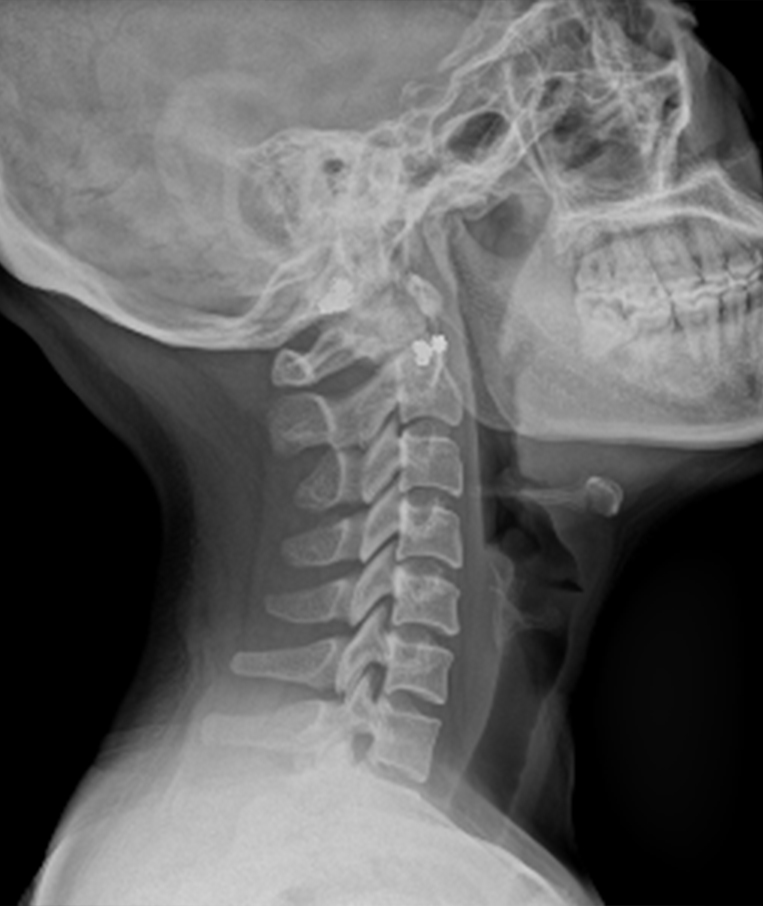

Clinical picture

临床图片